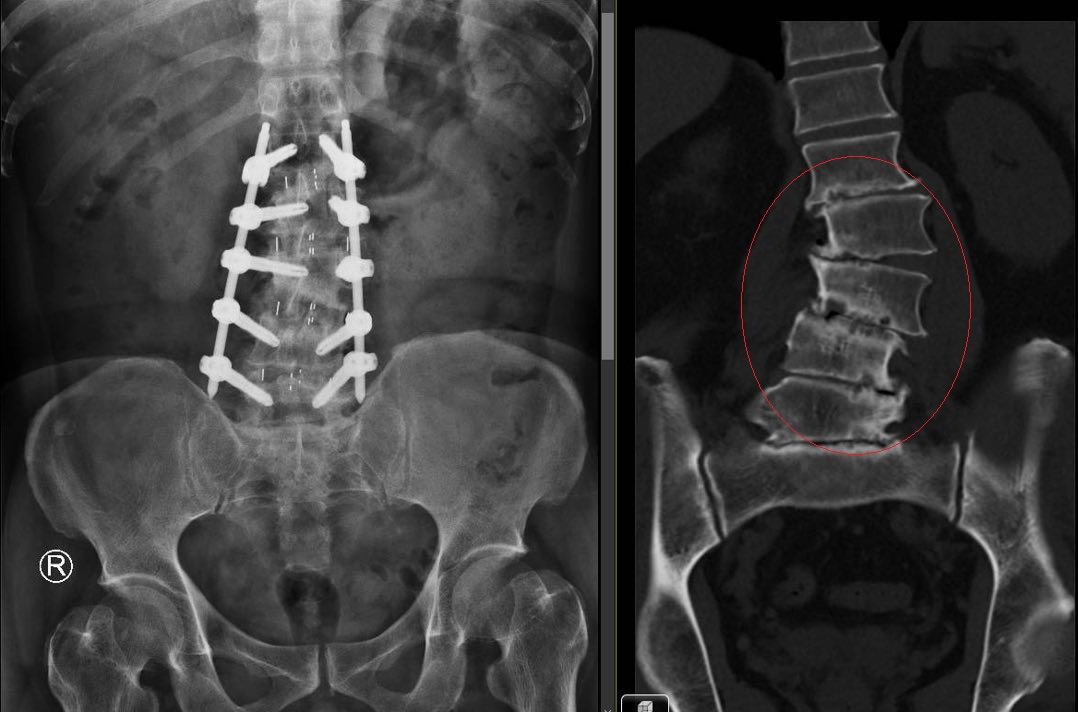

然而,肝臟會隨呼吸上下移動,為了精準定位腫瘤、避免傷及周圍正常肝臟與腸胃道器官,治療前會以儀器壓迫橫膈膜限制腫瘤的移動範圍,並進行三組電腦斷層掃描:包括一組標準速度、兩組慢切掃描,藉此觀察腫瘤在整個呼吸週期中的位置與移動範圍。待描繪腫瘤與正常組織、完成劑量計算後,每次治療前搭配即時影像導引技術,使用3D電腦斷層比對腫瘤及軟組織位置,提高放射治療準確度。常佑康醫師提及,這項治療適用於無法手術切除腫瘤的病人,由於放射劑量會一併影響鄰近腫瘤周圍的正常組織,因此病人正常肝臟體積必須足夠、肝功能相對良好才可安全施行。小腫瘤以SBRT治療有機會完全消失,另可應用於較大腫瘤的橋接治療,即先給予SBRT使腫瘤縮小,再銜接至手術切除或肝臟移植。國外研究指出,SBRT治療肝癌的五年局部控制率高達82%,5年存活率也有明顯提升。除肝癌外,SBRT也被運用於肺癌的治療。